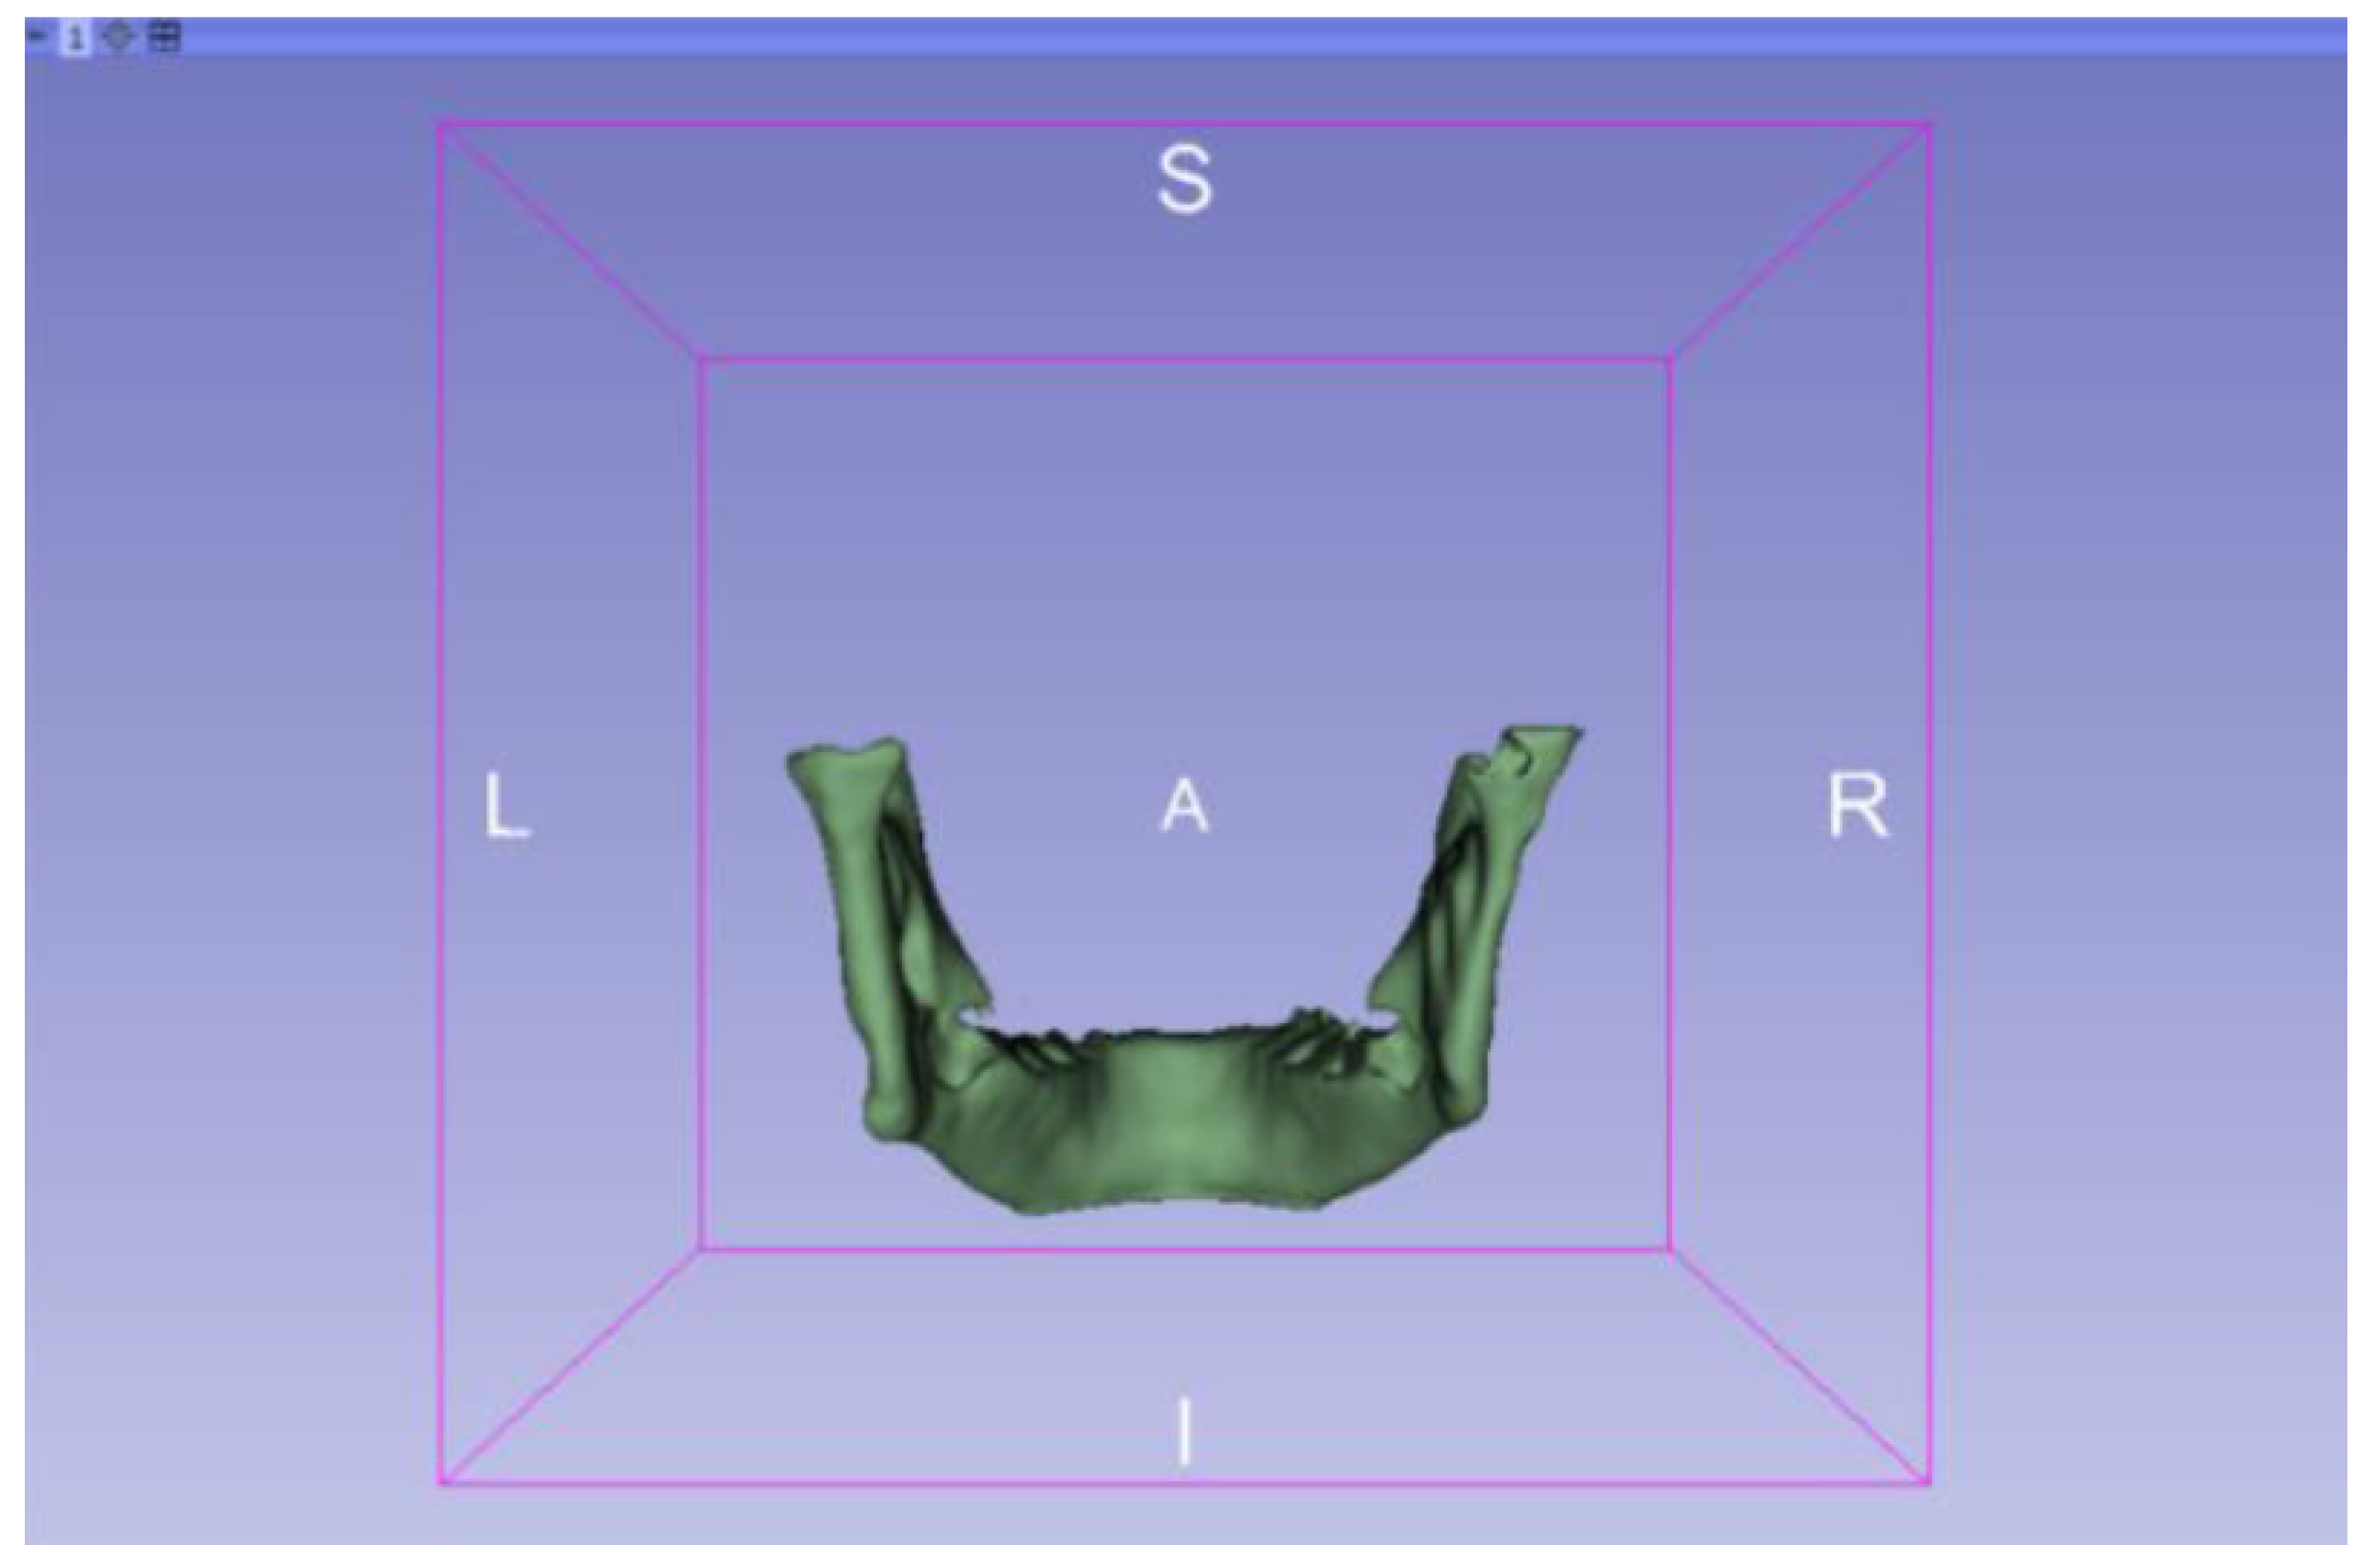

3.2. Human Lower Jaw

3.2.1. DICOM-to-STL Files